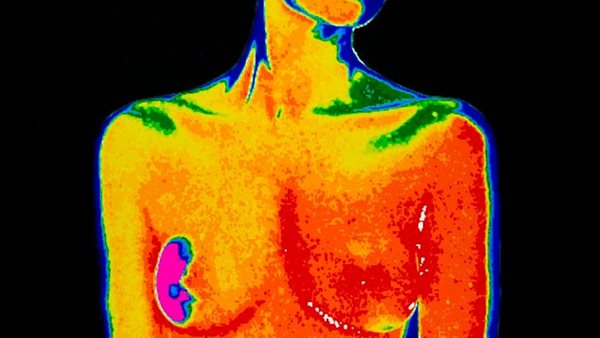

وتم إطلاق نظام جديد لتصوير الثدي بالأشعة السينية واختبارات الجينات والفحوصات، ومن خلاله يمكن أن يُكتشف المزيد من السرطانات، ويجنب النساء ضائقة الإنذار الكاذب، في محاولة لمعالجة المخاوف طويلة الأمد من أن النظام عرضة للإنذارات الكاذبة.

وبدلًا من إجراء مسح ضوئي واحد، سيُعرض عليهم مجموعة من الاختبارات لتحديد درجة شخصية لخطر الإصابة بسرطان الثدي، مع استخدام النتائج لتحديد موعد حضورهم الفحص التالي.